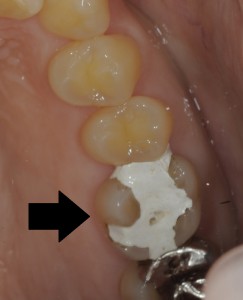

また、下の写真は、虫歯が大きく歯の神経が腐敗していたため、神経の治療の後にダイレクトボンディング/コンポジットレジン修復を行い、修復したケースです。

(左: 治療前 右: 治療後)